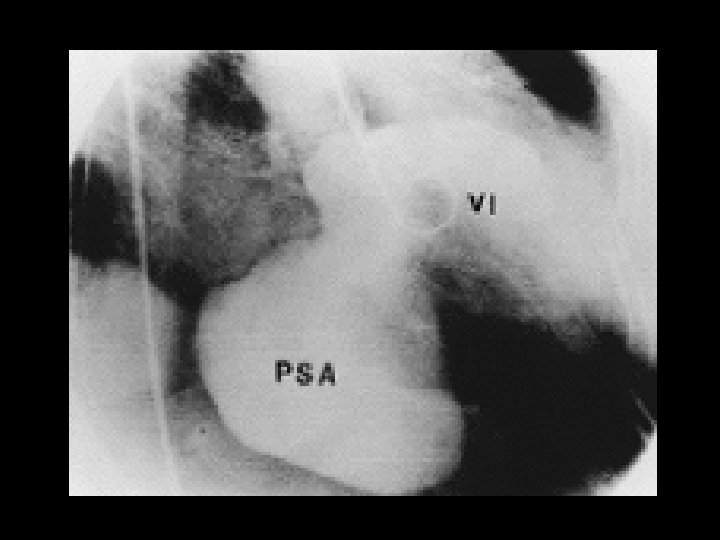

Clínica y diagnóstico o Métodos de diagnóstico por imágenes n Ventriculografía izquierda n Ecocardiografía n TAC n Resonancia magnética

Clínica y diagnóstico o El primer signo de ruptura septal ventricular en post-infarto es la aparición de un soplo pansistólico. Borde esternal inferior izquierdo. RX Tórax: hipertensión venosa pulmonar y aumento del flujo sanguíneo pulmonar.

Clínica y diagnóstico o o El soplo puede ser resultado de una CIV o de insuficiencia mitral, ambas condiciones pueden coexistir. Ecocardiograma (TT o TE): Alta sensibilidad y especificidad, seguro, y rápido.